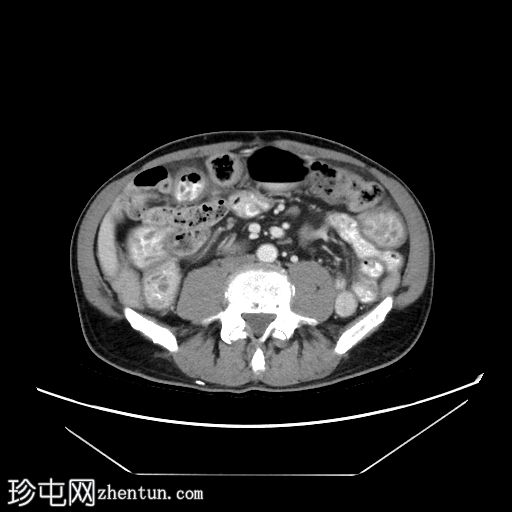

轴向C+门静脉期

冠状C+门静脉期

十二指肠和空肠皱襞弥漫性低衰减结节性增大增厚,

造影剂(阳性)增强。微量腹水。

左侧少量积液,伴轻度胸膜增厚。良性肾脾囊肿。骨髓异质性。

这是酪氨酸激酶抑制剂 (TKI) 相关小肠淋巴管扩张的典型表现,是癌症再分期时需要注意的独特副作用。此类药物可导致小肠和大肠淋巴管扩张,从而引起胃肠道症状。